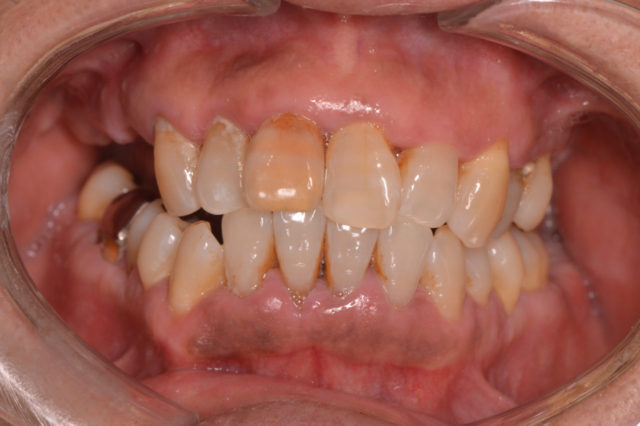

before

年齢 50代 性別 女性 主訴 「最近、歯がグラグラしてきて、このままだと抜けてしまいそう…」という不安から、当院に初めてお越しくださいました。

お話を伺うと、歯科医院へは痛みがあるときにだけ通院されていたそうで、なんと10年ぶりの歯医者さんとのことでした。治療 ■初診時の状態

歯ぐきは赤く腫れ、出血や歯石の沈着が確認されました。

歯周ポケットも深く、中程度の歯周病と診断。将来的には歯を失うリスクが高い状態でした。

■治療後の変化

歯ぐきが引き締まり、出血や腫れが改善

歯のグラつきも軽減

何より「子どもに口臭を指摘されなくなりました!」といううれしいお声をいただきました